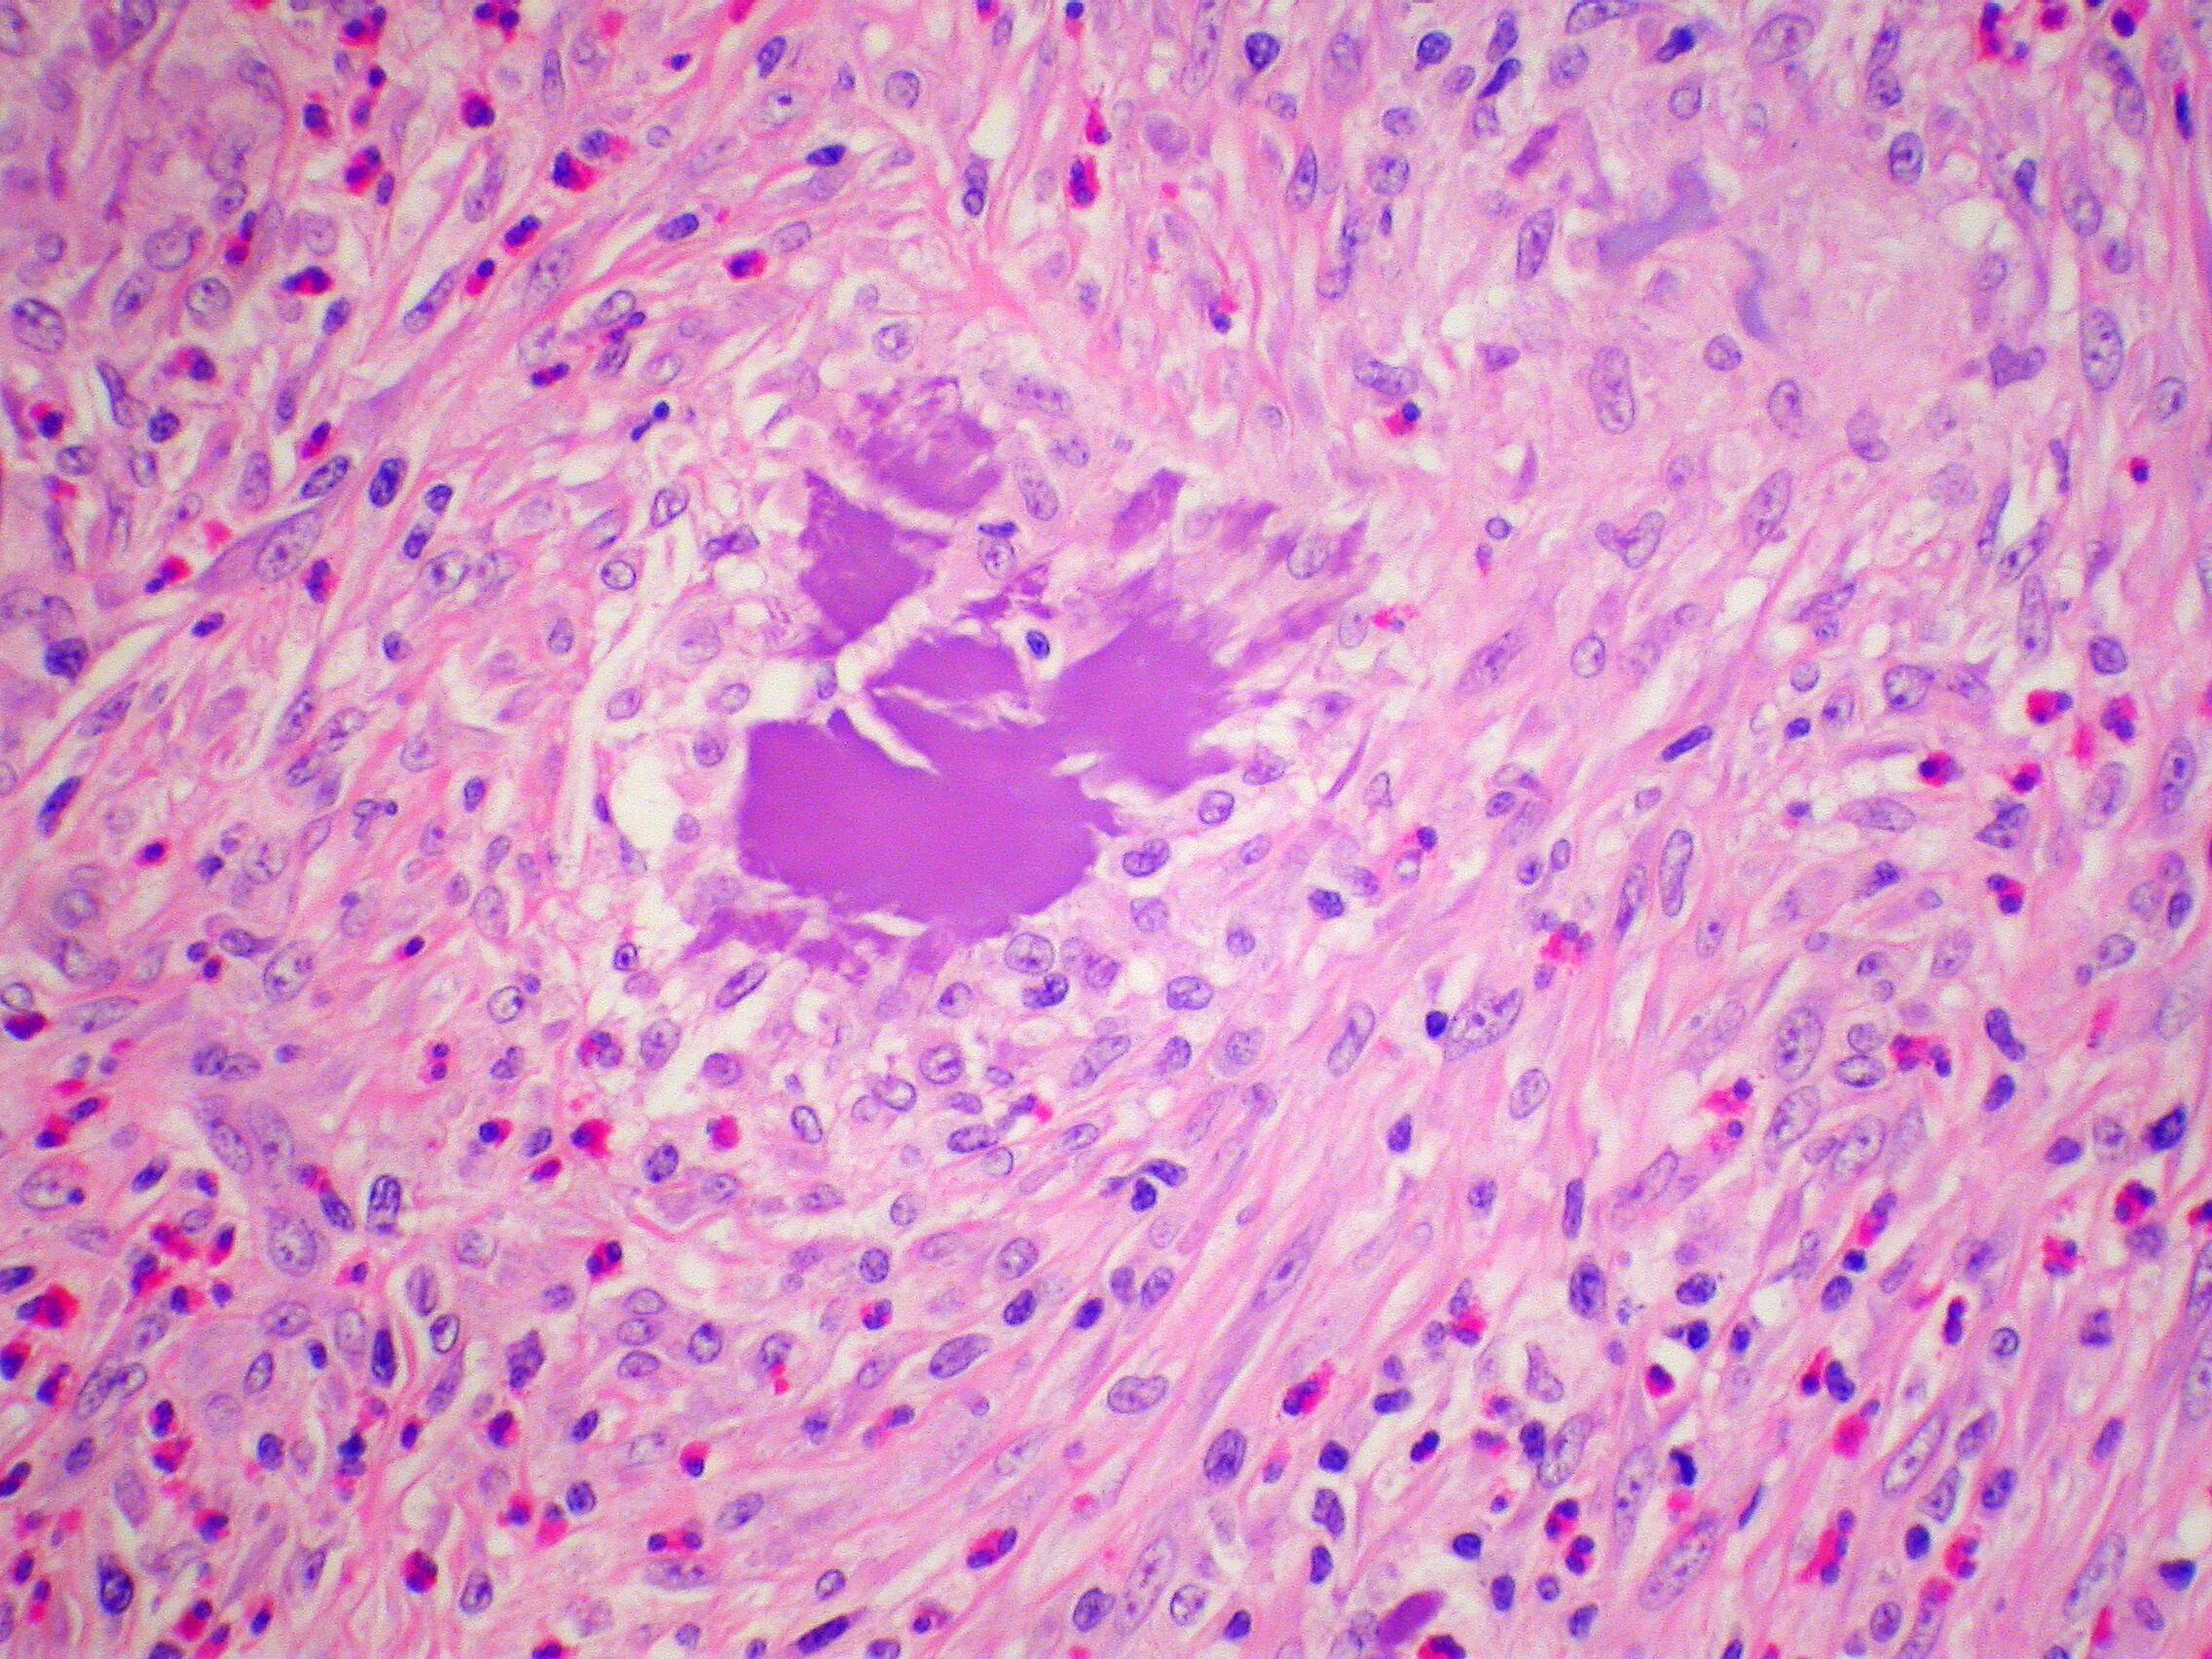

Клетка типа инородных тел